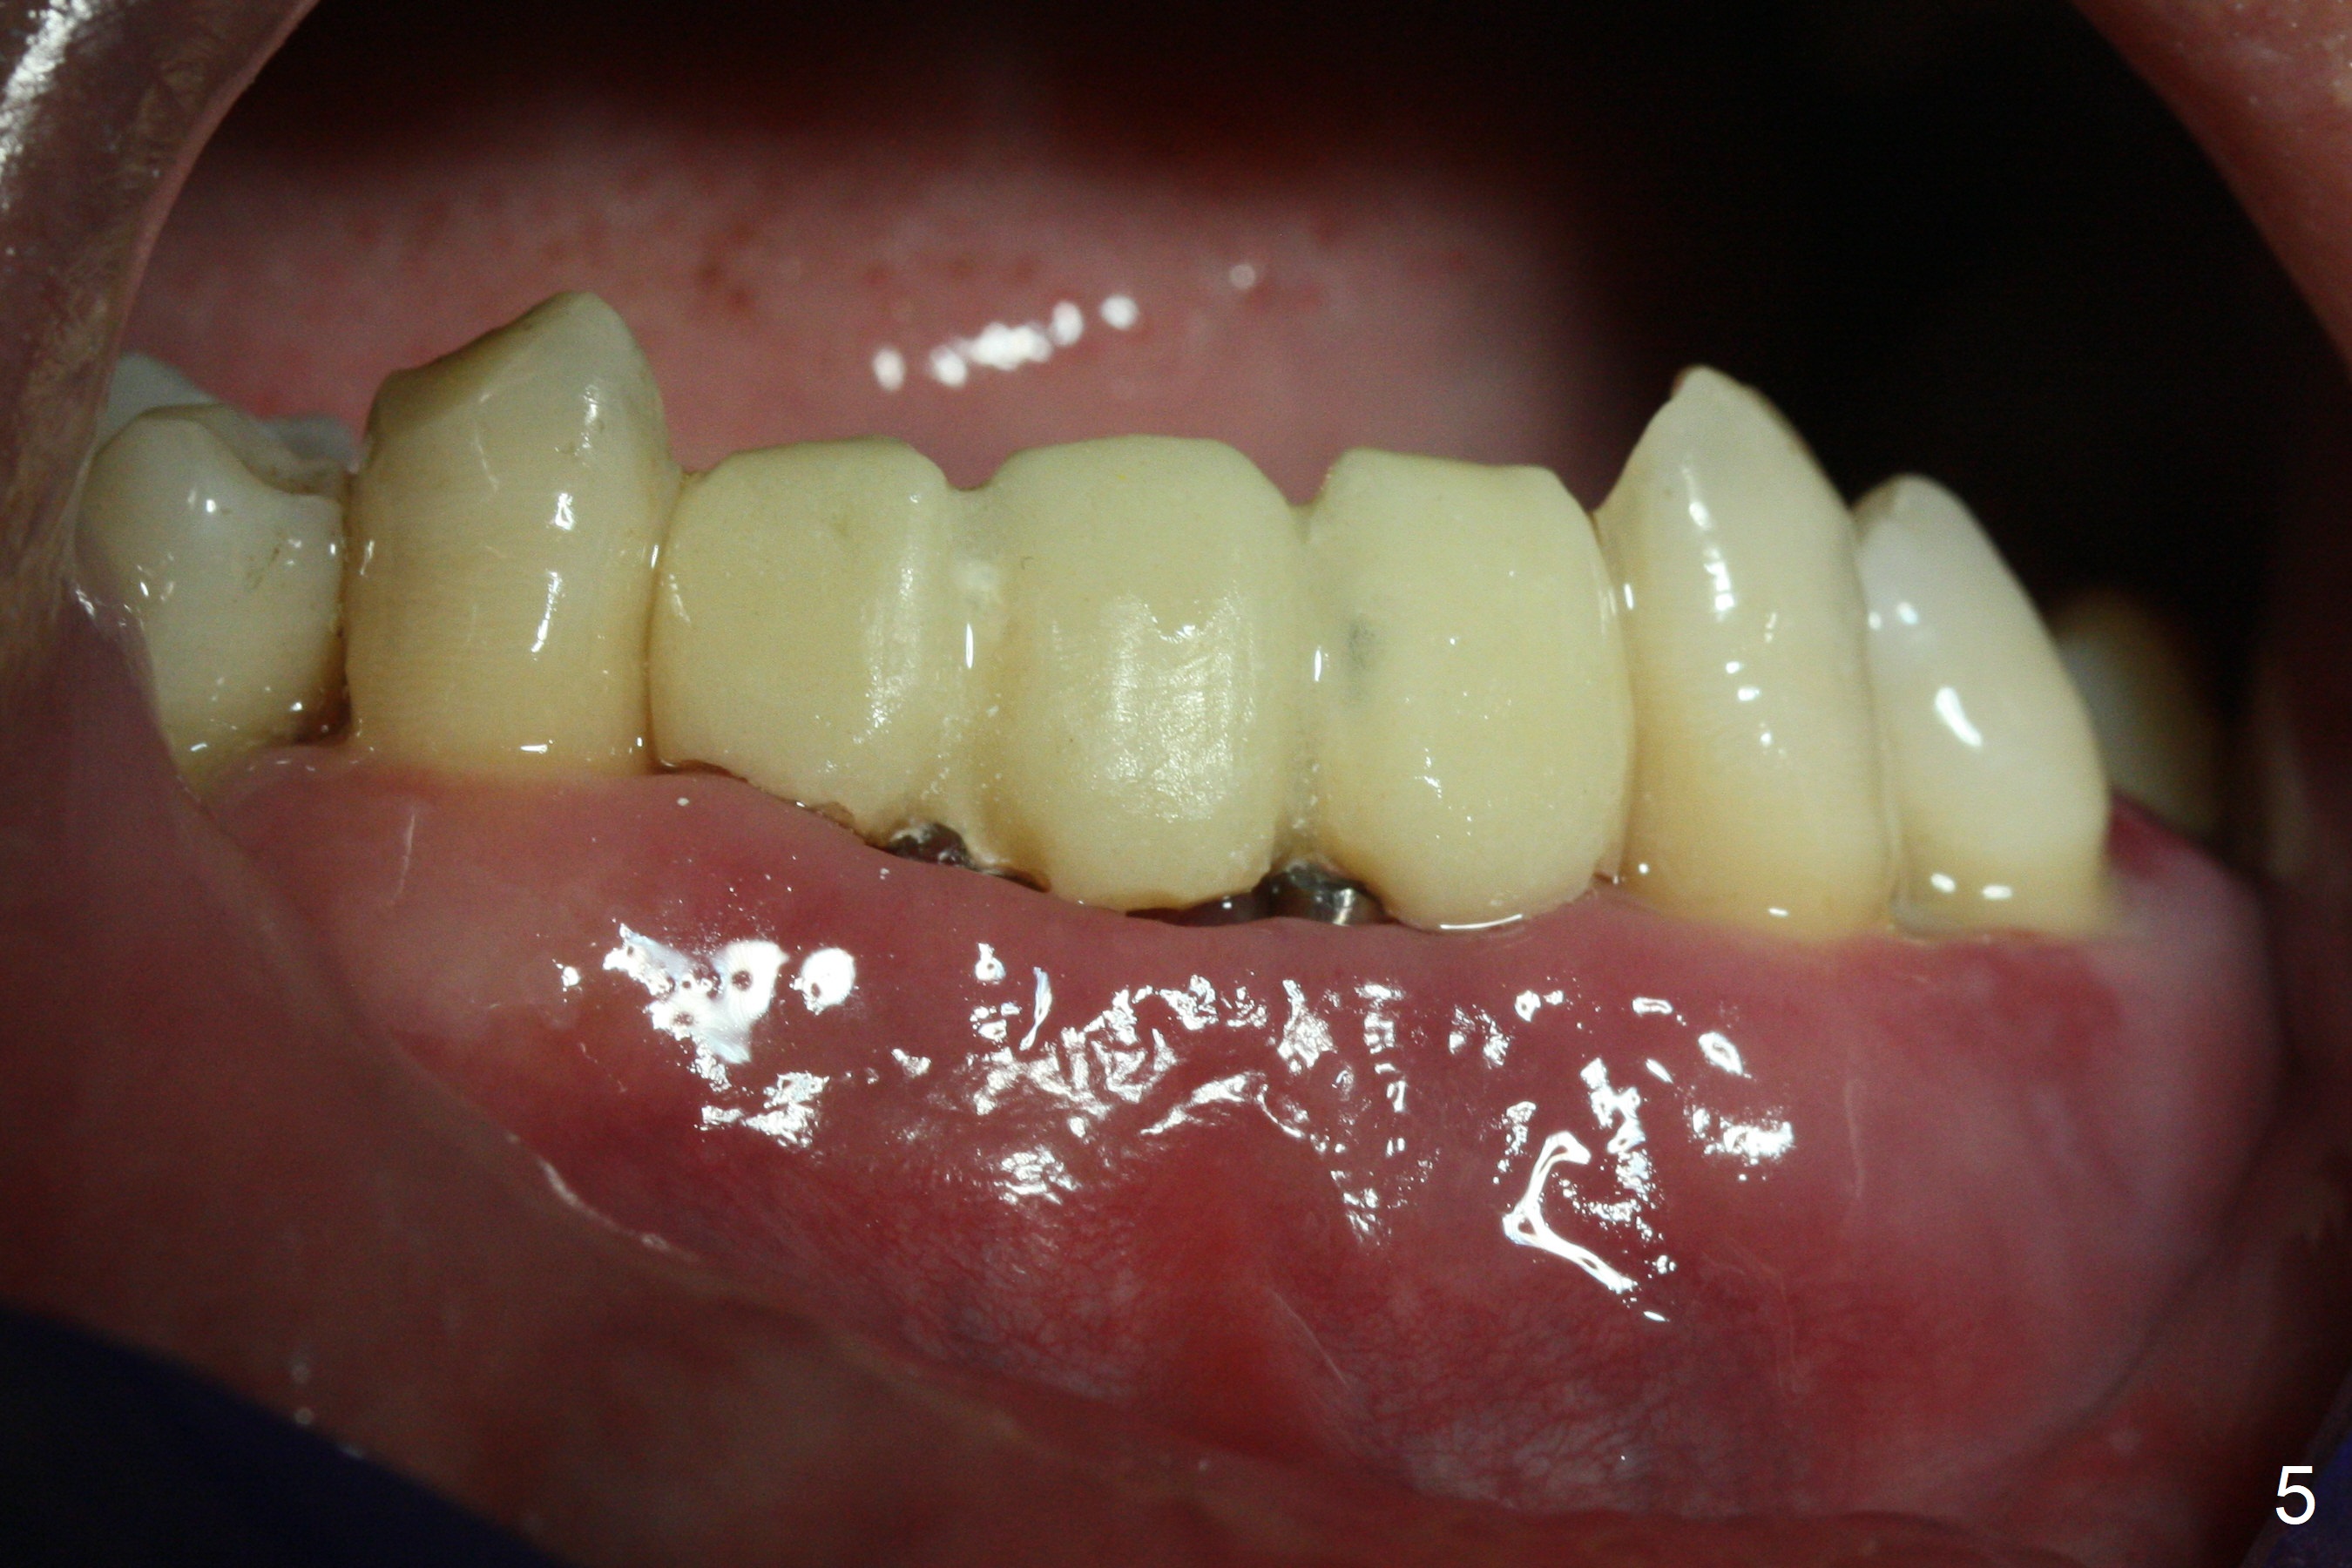

The 36-year-old man (ex-smoker, quit for 4-5 years) insists upon #3 and 5 extraction first for implants, in spite of more severe infection at #7, 14,19,30 (Fig.1-4). The gingiva around #23-26 implants is healthy 3 weeks postop (Fig.5). The initial depths at #3 and 5 are 8.5 mm (bone-level) and 18 mmm (gingiva-level (13 mm (implant length) + 5 mm cuff), respectively. When a drill penetrates the sinus floor, confirm the depth. After use of 3.8 mm drill, 4.5 mm tap drill is inserted at #3 without stability, while a 4.5x13 mm implant is placed at #5 with primary stability (Fig.6,7). Then a 5x11.5 mm is placed at #3 subcrestal proximally after sinus lift with Vanilla graft (without sinus membrane perforation; Fig.8). The implant at #5 is seated ~1 mm deeper (subcrestal mesially (^^); supracrestal distally (^)); allograft is placed around the implants prior to insertion of 6.5x7(5) and 5.5x4(5) mm abutments; last more allograft is added (Fig.9 *, 10). The implants seem to have been osteointegrated 4.5 months postop (Fig.11,12). The gingiva is healthy around the implants without bone loss 3 months post cementation (Fig.13,14).